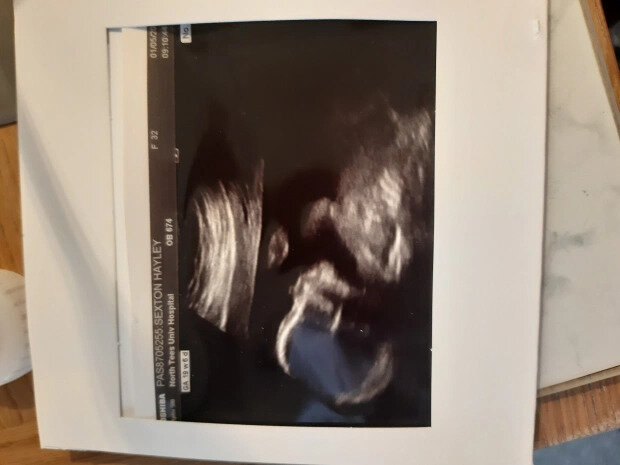

33-летней Хейли Секстон во время беременности дважды сказали, что у нее будет девочка. Женщина покрасила детскую в розовый цвет, выбрала для дочери имя Изабелла и написала его на стенах комнаты.

«Когда акушерка сказала: «Он родился», я подумала: «В смысле?» На двух УЗИ мне сказали, что у меня будет девочка. Но когда ребенка протерли и показали мне, я увидела, что это мальчик!», - рассказывает молодая мать.